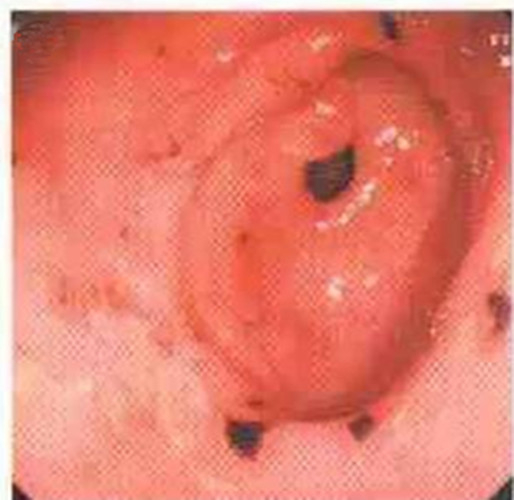

成人慢性胃炎